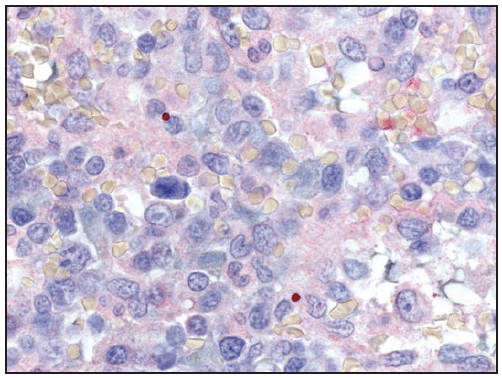

Ehrlichiae are obligate intracellular bacteria that infect peripheral blood leukocytes. E. chaffeensis, the pathogen that causes human monocytic ehrlichiosis, predominantly infects monocytes and tissue macrophages ( Figure 27). The organisms multiply in cytoplasmic membrane-bound vacuoles, forming tightly packed clusters of bacteria called morulae. In patients with fatal E. chaffeensis ehrlichiosis, systemic, multiorgan involvement has been described with the greatest distribution of bacteria in the spleen, lymph nodes, and bone marrow (128). Unlike in RMSF, direct vasculitis and endothelial injury are rare in ehrlichiosis. The host systemic inflammatory response, rather than direct effects of the pathogen, is likely to be largely responsible for many of the clinical manifestations of ehrlichiosis (129).

Laboratory Findings

Characteristic laboratory findings in the first week of E. chaffeensis ehrlichiosis include leukopenia (nadir usually 1,300–4,000 cells/µL) (129), thrombocytopenia (nadir usually 50,000–140,000 platelets/µL, although occasionally <20,000 platelets/µL), and mildly or moderately elevated levels of hepatic transaminases. Anemia occurs later in clinical illness and is reported in 50% of patients (129). Mild-to-moderate hyponatremia might also be present (128). During the recovery period, a relative and absolute lymphocytosis is seen in most patients (155). In some cases, pancytopenia due to ehrlichiosis has prompted bone marrow aspirate and biopsy, which typically reveals normocellular or hypercellular marrow (128,156). In some patients, morulae might be observed in monocytes in peripheral blood (157) ( Figure 28) and occasionally in CSF (158,159) or bone marrow. In this context, a routine blood smear can provide a presumptive clue for early diagnosis; however, the visualization of morulae still requires confirmatory diagnostic testing (see Confirmatory Diagnostic Tests). When CSF is evaluated, a lymphocytic pleocytosis is most commonly observed, although neutrophilic pleocytosis also can occur (128,135). CSF white blood cell counts are typically <250 cells/µL but can be higher in children (128,135,158). Elevated CSF protein levels are common (135).